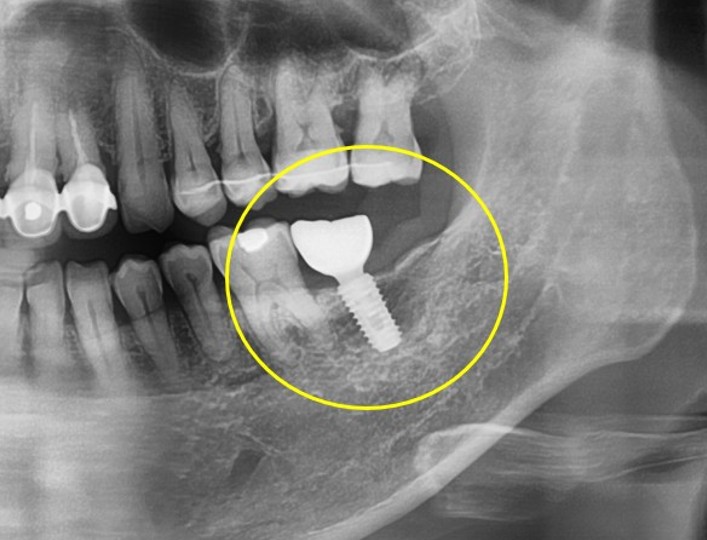

임플란트/틀니